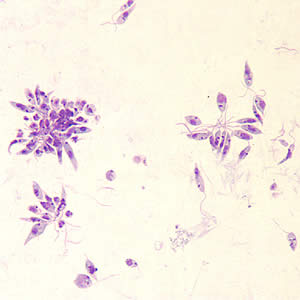

Giardia lamblia

“wearing glasses” appearance with axostyles down the middle